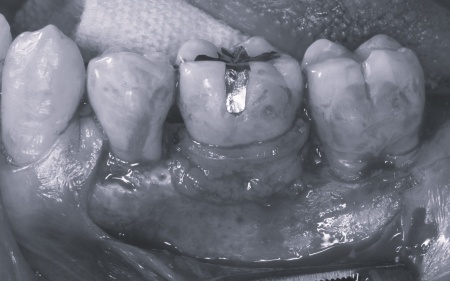

②矯正治療後、歯周病を発症している左下奥歯(第1大臼歯)を温存するために、失われた骨や歯茎を再生する「歯周再生療法」を行う

まずは歯の移動スペースを確保するために、計6本の歯を抜きます。

その後、上下の歯の表面にブラケットを接着し、上顎にはトランスパラタルアーチを、下顎にはミニインプラントを使用しながら、マルチブラケット矯正を開始しました。

その後、左下奥歯に歯周再生療法を行って歯周病が改善したことを確認し、治療を終了しました。